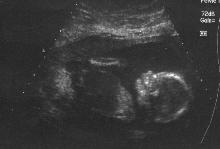

This is our Baby Girl, we just found this out today and that everything with the Pregnancy is going just fine.

This is a HUGE load off our shoulders. Almost half way there, 19 weeks 2 days.